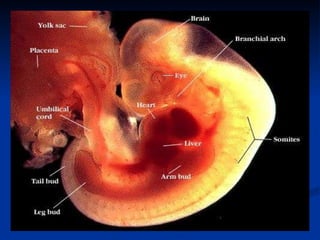

The document discusses embryonic development in humans. It begins with fertilization and cleavage, followed by gastrulation where the three germ layers are formed. During this time the primitive streak and Henson's node develop. Organogenesis then occurs, forming individual organs from the germ layers. Mammalian development includes the allantois and notochord. In humans, the placenta forms and gestation occurs over three trimesters, with major organ structures present by the first trimester.